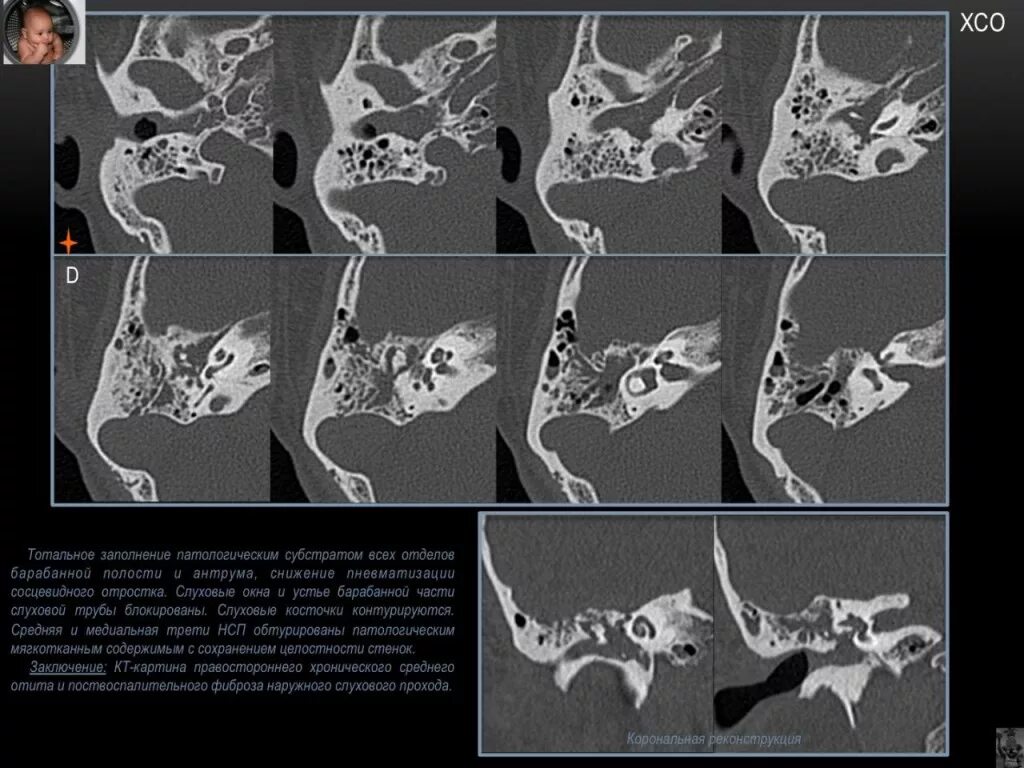

Патологическое содержимое что это